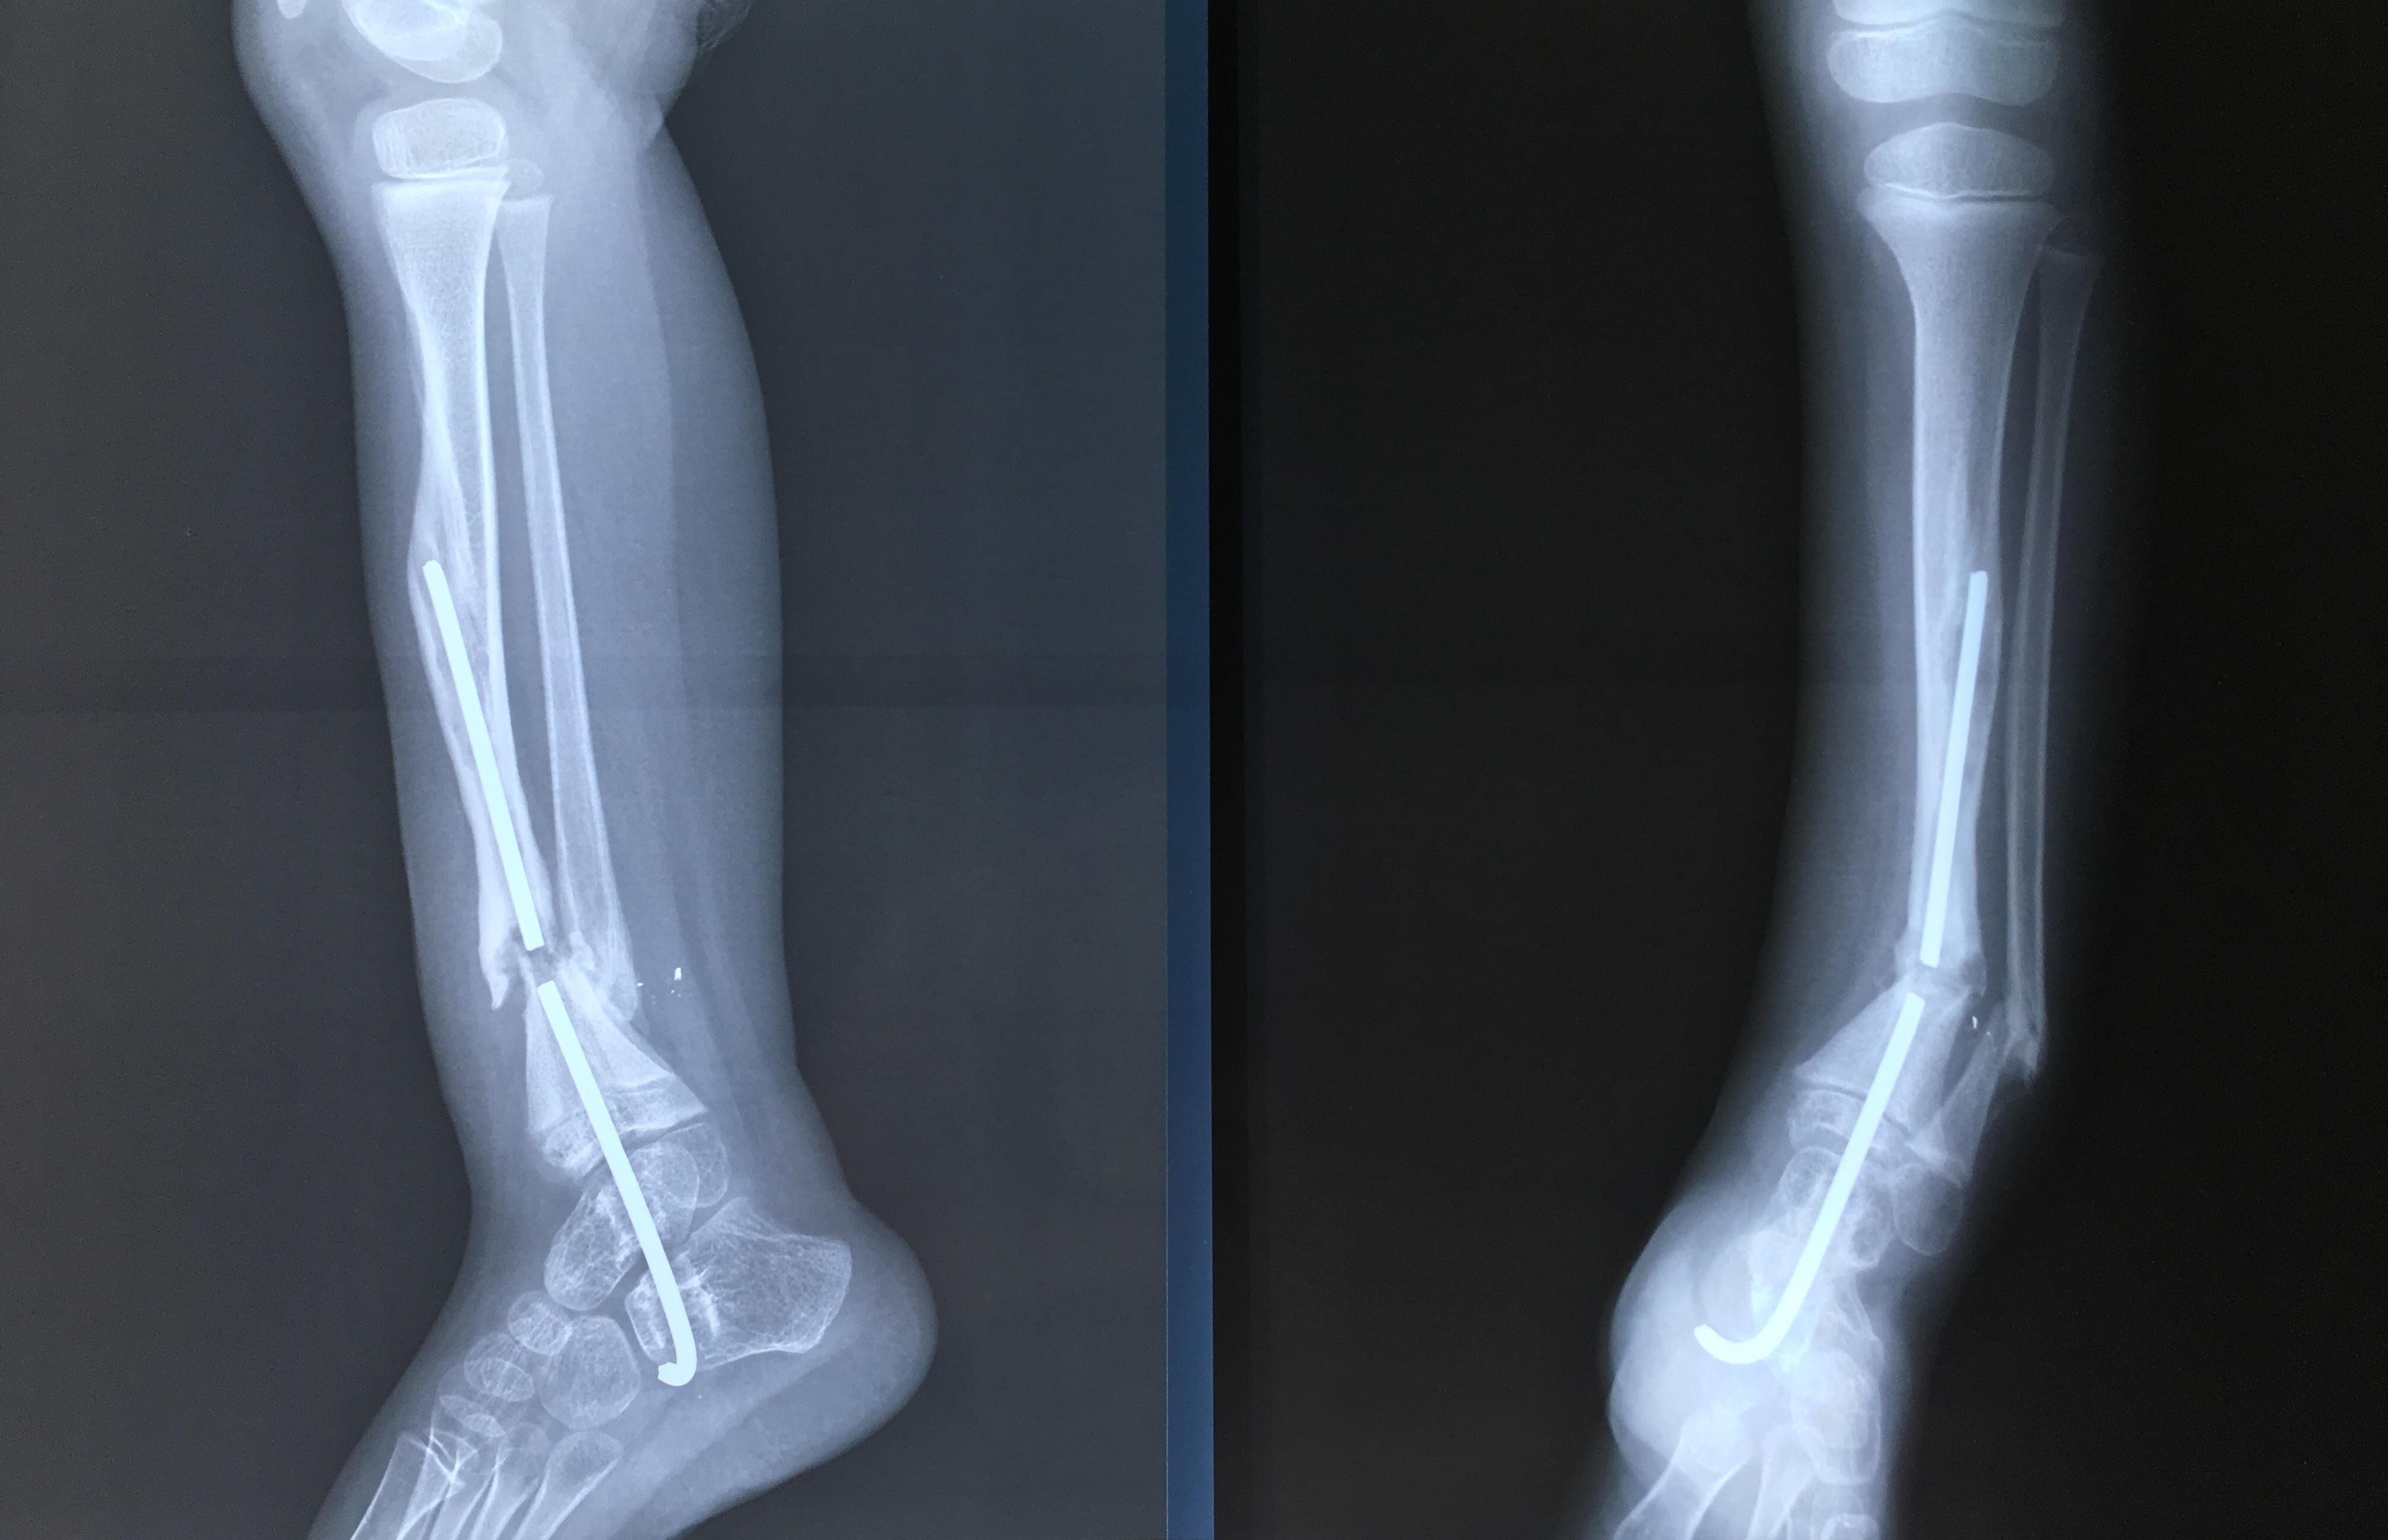

Phẫu thuật thành công ca bệnh hiếm gặp...khớp giả bẩm sinh xương chày

26/06/2019 17:00

Đã xem: 3330

Bệnh viện Chấn thương- Chỉnh hình Nghệ An, vừa phẫu thuật thành công cho bệnh nhi khớp giả bẩm sinh xương chày